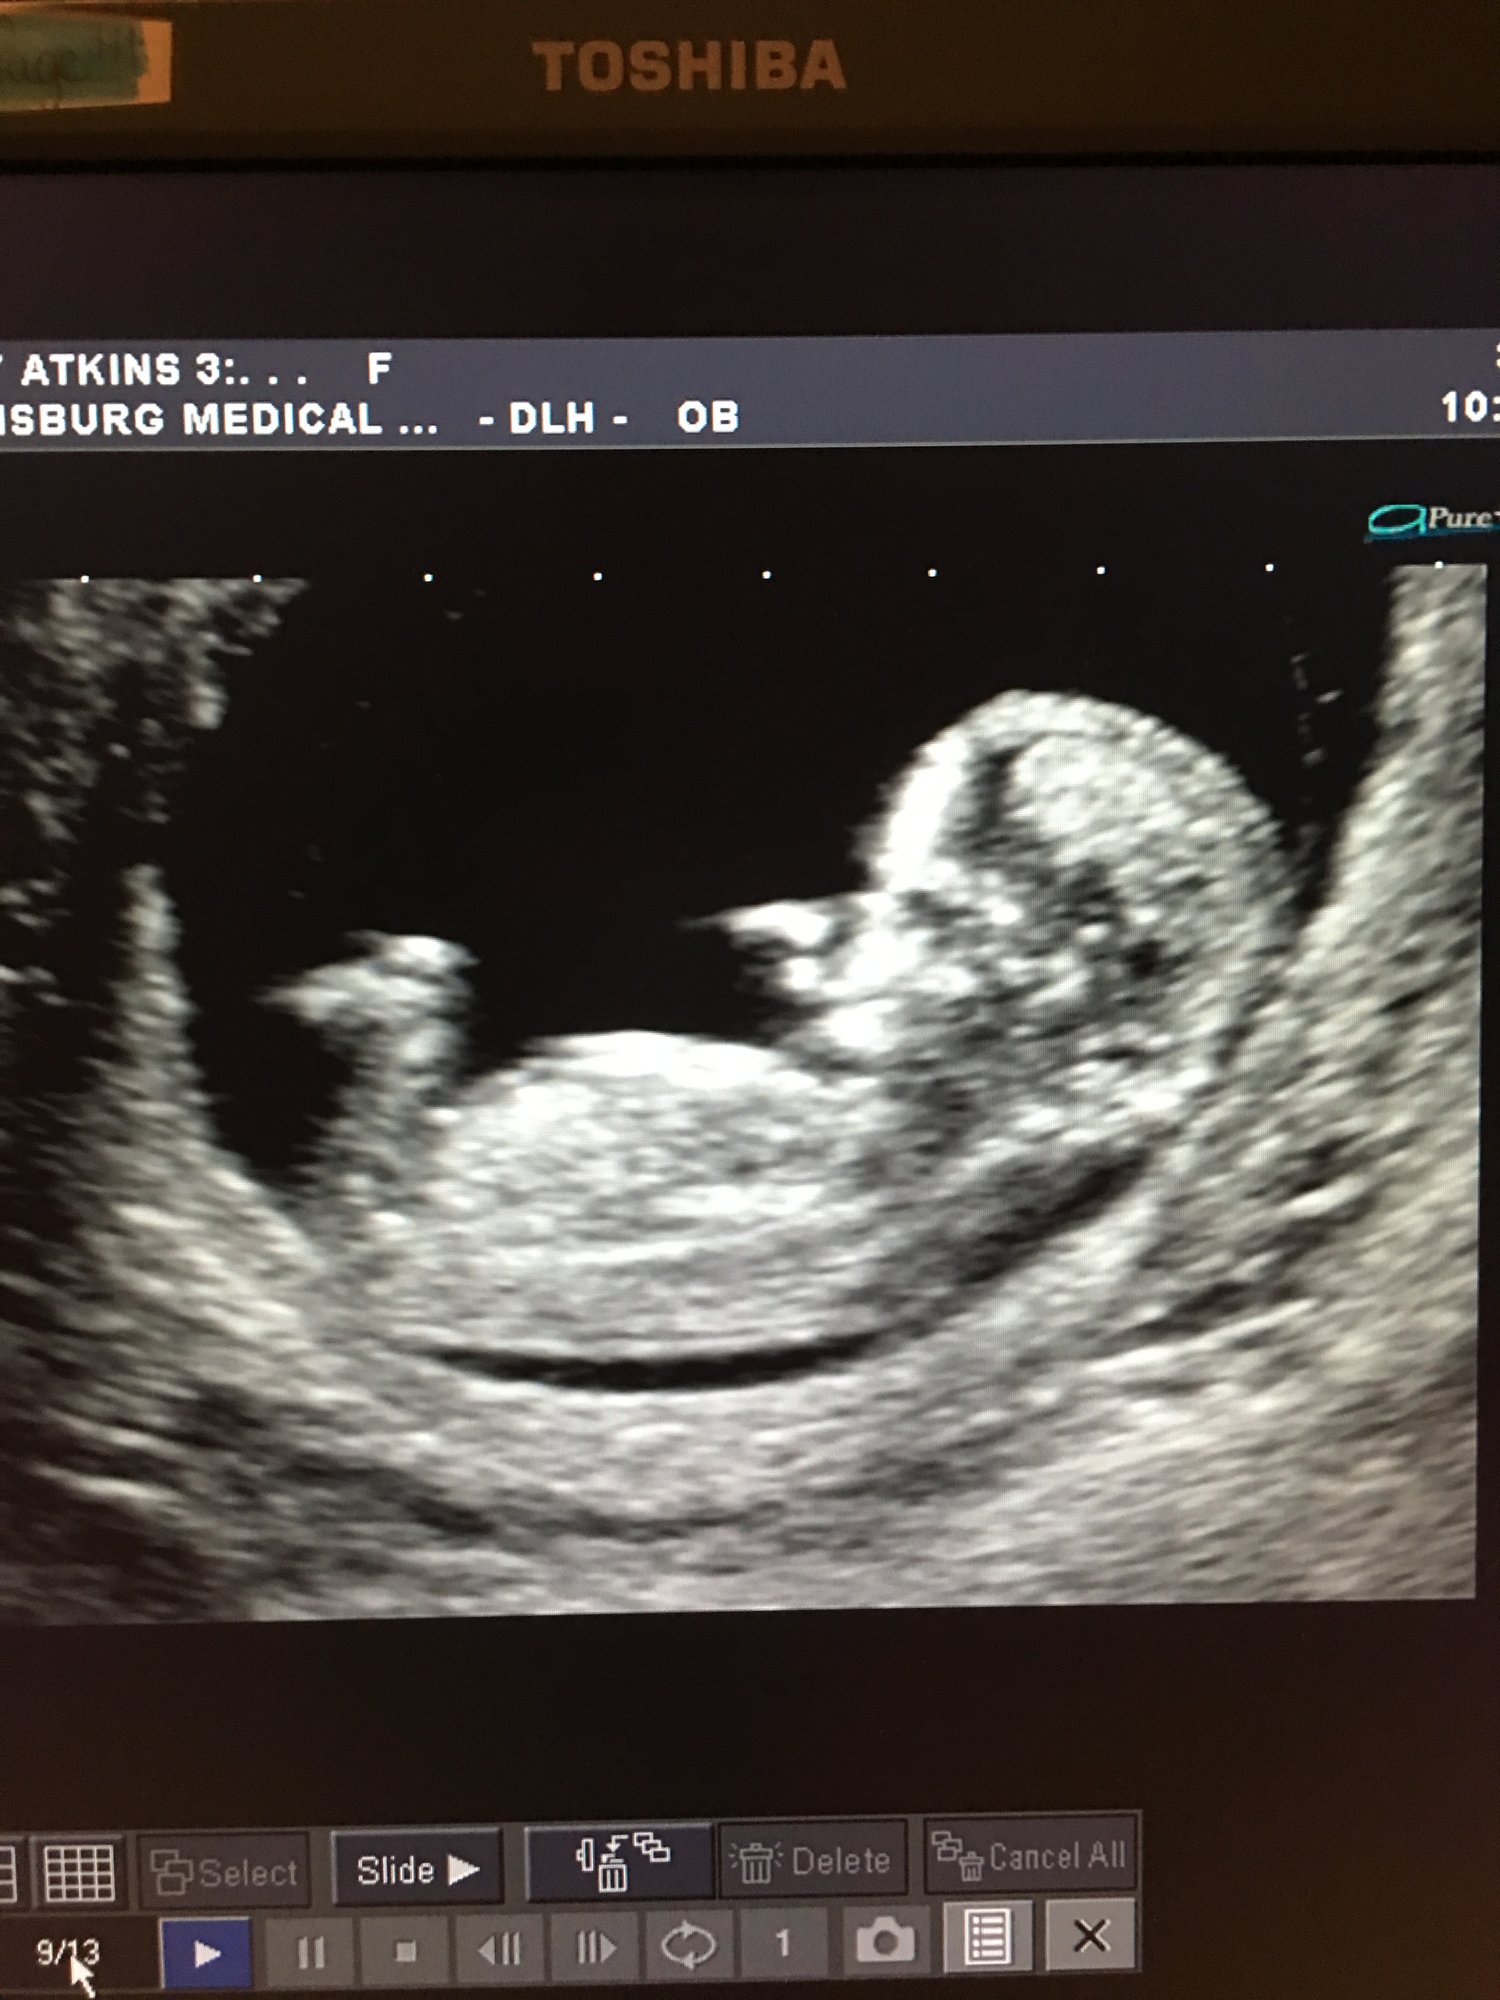

This will be my 3rd child. Got to see my baby via handheld ultrasound! They didn't have this when I was pregnant with my first back in 2010. Due 09/30 and super excited!